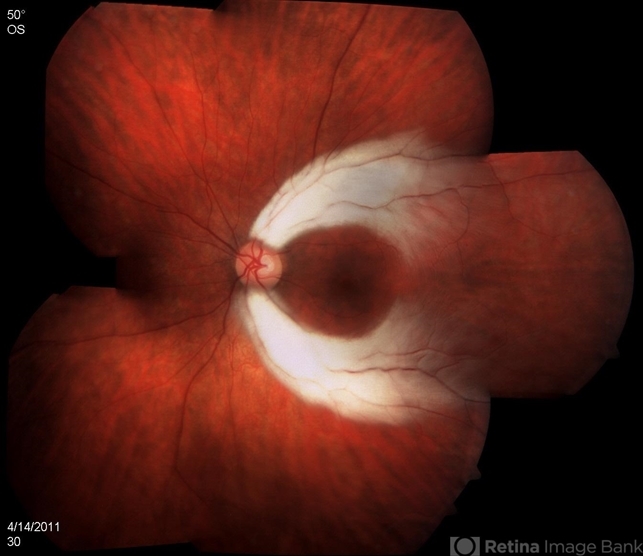

- myelinated nerve fibers, fundus photograph

- Left eye of a 20-year-old female with myelinated nerve fibers.